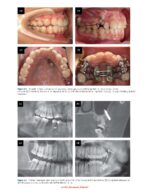

Although numerous case reports demonstrate the versatility of TADs (e.g., incisor intrusion, molar distalization or protraction, molar intrusion, skeletal expansion, and maxillary protraction), many clinicians struggle with:

• Identifying the optimal mini-implant insertion sites for specific tooth movements

• Lacking confidence in placing mini-implants in anatomically challenging areas, even when they understand the theory